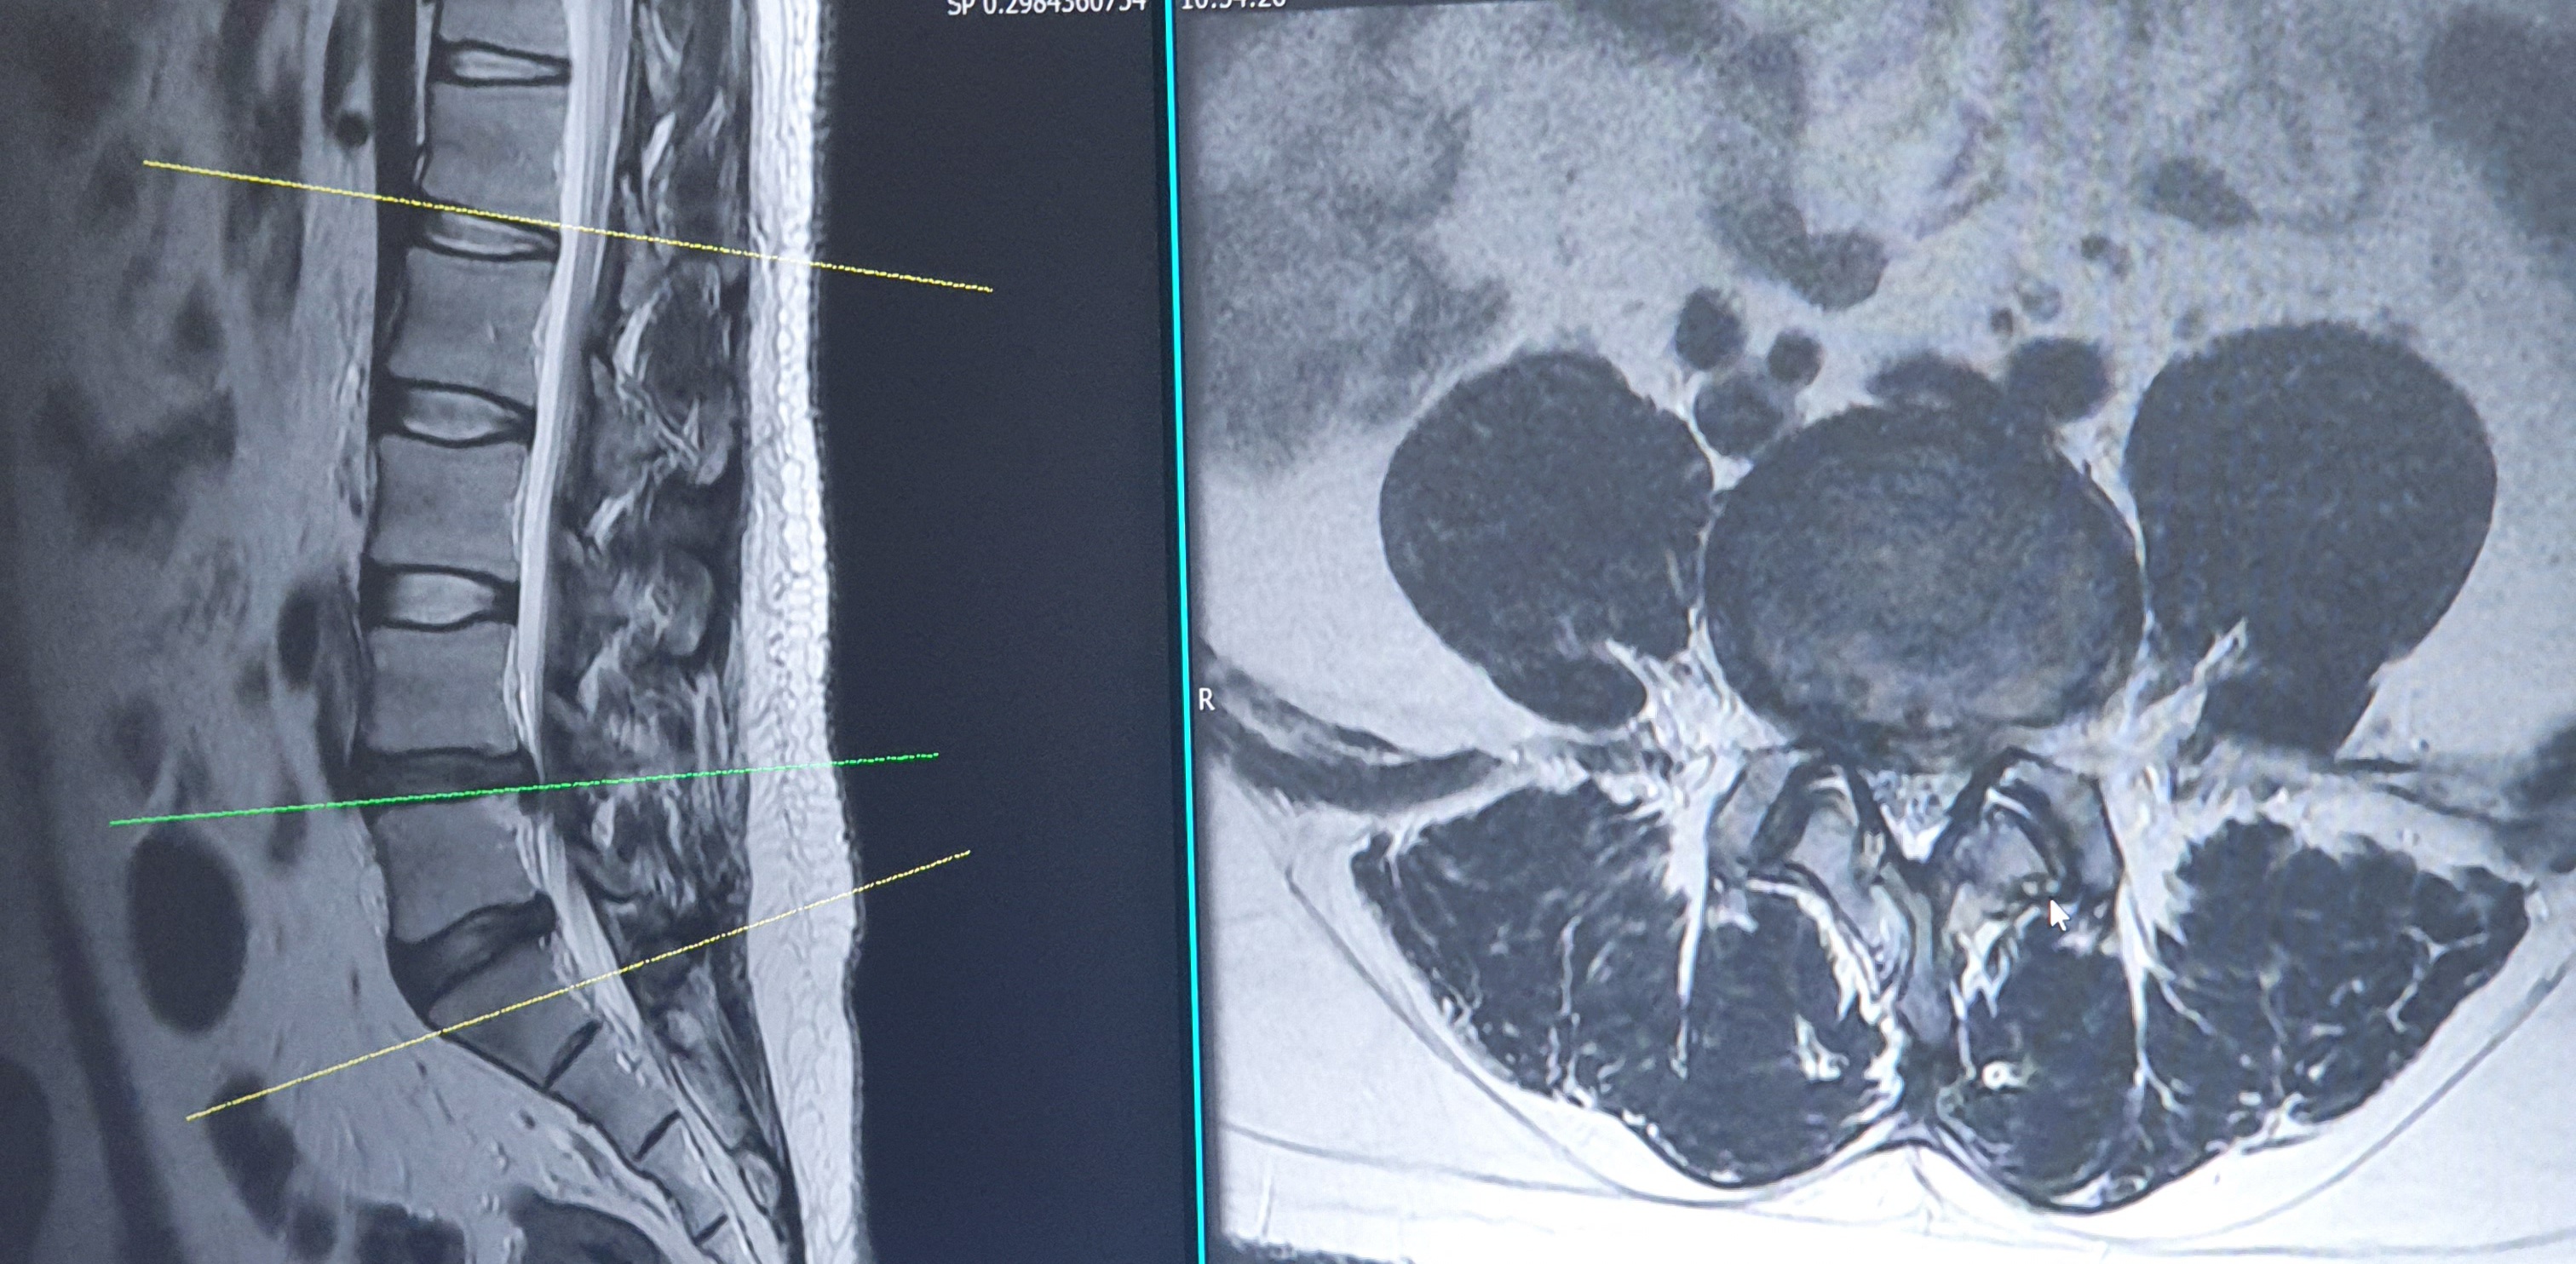

허리디스크는 척추 뼈 사이에 위치한 연골과 같은 구조물인 디스크가 손상되어 발생하는 상태입니다. 보통 나이가 들어감에 따라 이러한 문제가 발생하는 경향이 있지만, 무리한 운동이나 잘못된 자세로 인해 젊은 사람들도 겪을 수 있습니다. 허리디스크는 척추 신경을 압박하여 여러 가지 증상을 유발할 수 있습니다.

허리디스크의 치료방법은 크게 비수술적 방법과 수술적 방법으로 나눌 수 있습니다. 비수술적 방법에는 물리치료, 약물 복용, 신경차단술 등이 포함됩니다. 물리치료는 근육을 이완시키고, 통증을 완화시키는 데 도움을 줄 수 있습니다. 또한, 약물복용을 통해 염증을 줄이고, 통증을 관리할 수 있습니다.

수술적 방법은 일반적으로 상태가 심각할 경우 고려됩니다. 수술은 디스크를 제거하거나, 척추를 고정하는 방법 등이 있습니다. 하지만 모든 환자가 수술이 필요한 것은 아니며, 개별의 상태에 따라 전문가의 진단을 받는 것이 중요합니다.